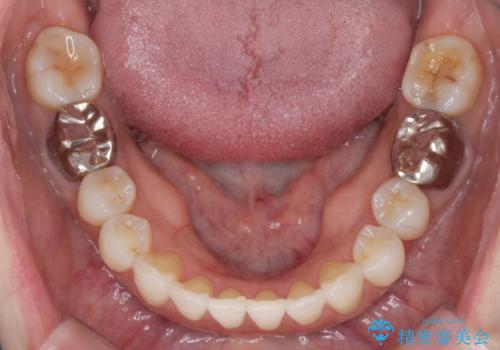

抜歯をせず前歯の角度を改善するマウスピース矯正治療

治療期間が約半年で行うことができ、歯を抜かずにマウスピース矯正で可及的に前歯の角度を改善する治療方針を

奥歯の状態等も鑑みて選択されました。

約半年で大きく前歯の角度を改善することができ、抜歯を行わない矯正治療の結果に大変喜んでいただくことができました。